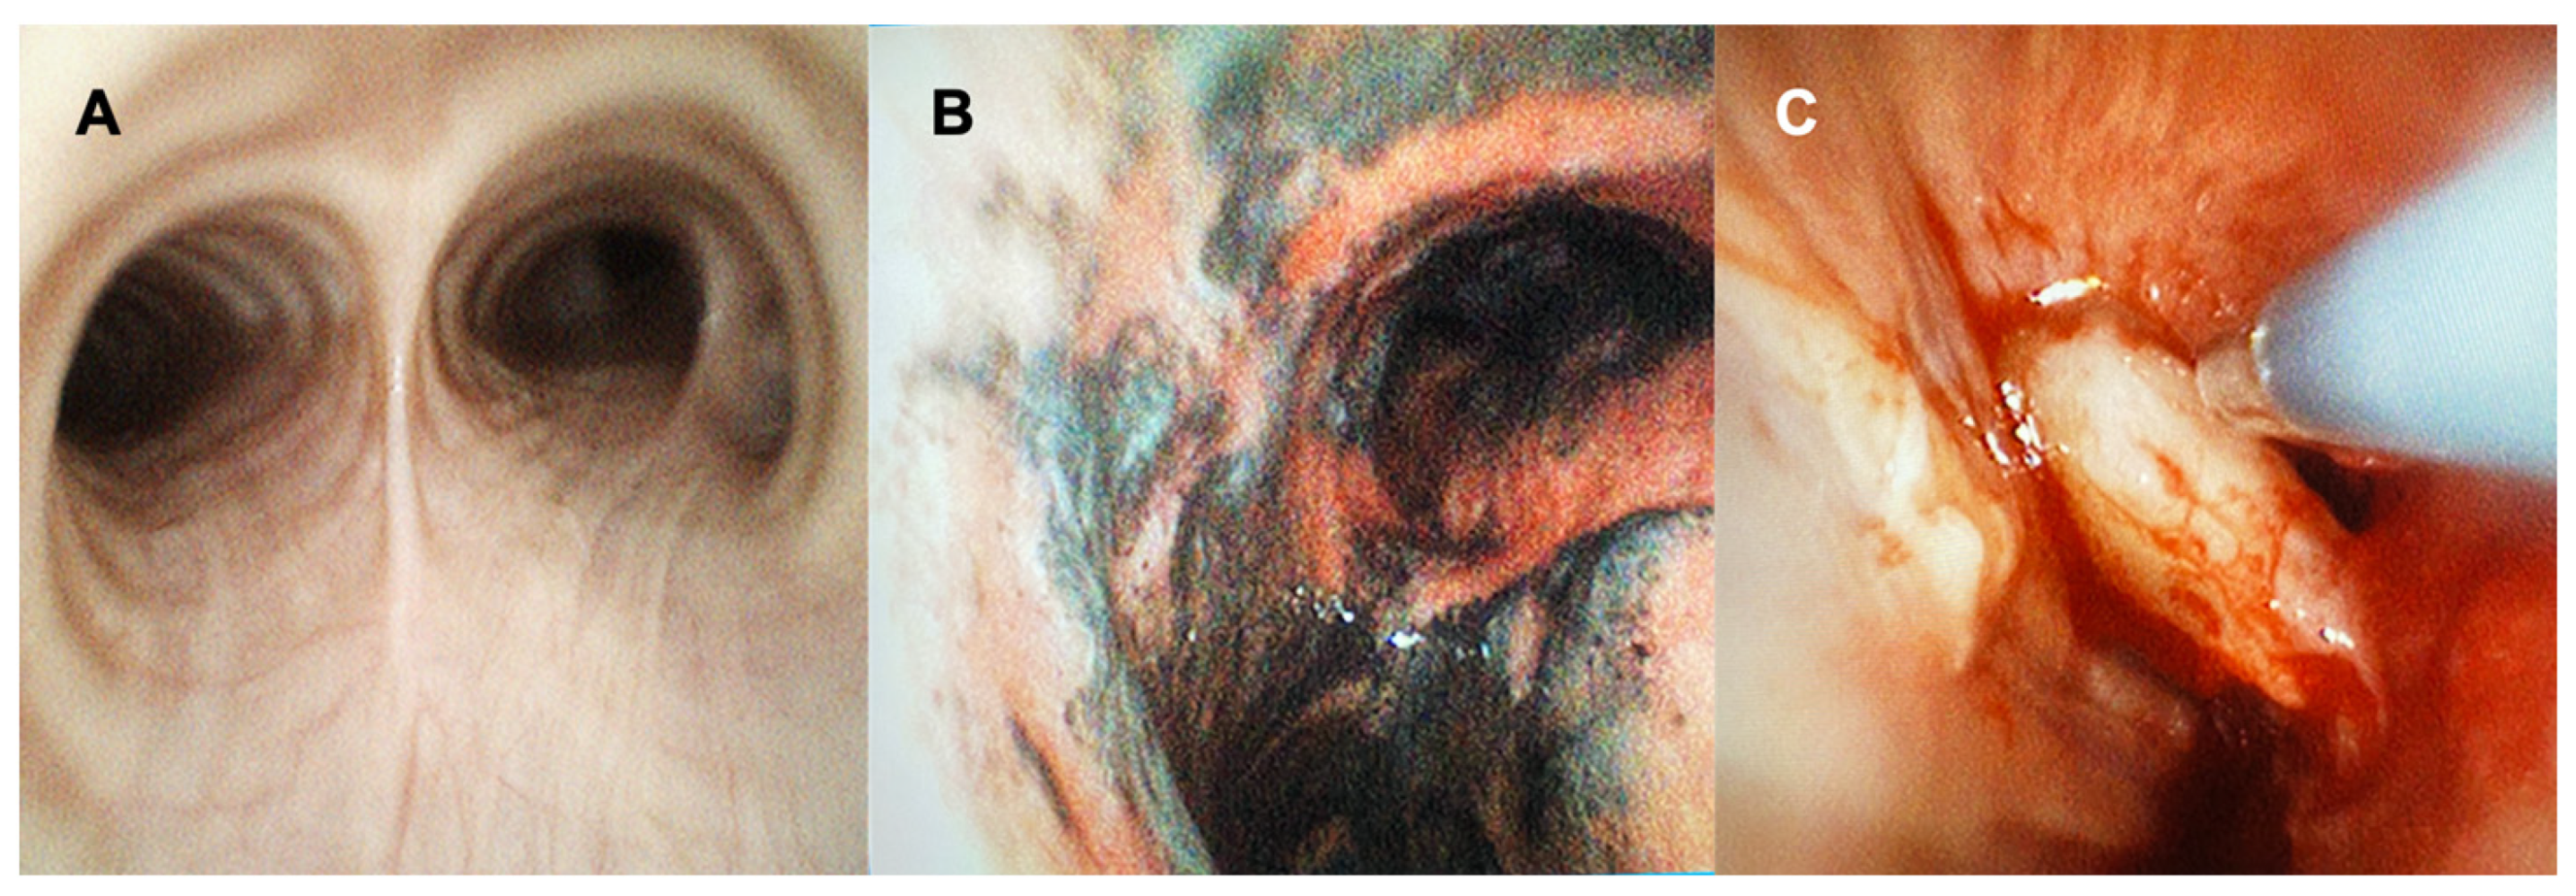

5. SUFB Use for Pulmonary Procedures

Bronchoscopic procedures such as simple airway inspection and bronchoalveolar lavage can be safely performed using the SUFB (Figure 1). Zaidi and colleagues demonstrated that cell yield and viability in BAL sample were comparable between SUFB and RFB, with greater sample volumes when using SUFB [20]. The authors concluded that SUFB are an acceptable and cost-effective option when compared with standard RFB for obtaining a BAL. Of note, recent studies which evaluated the feasibility, safety, navigation success, and diagnostic yield in sampling pulmonary lesions using the Monarch and Ion robotic navigational systems, used bronchoscopes that technically speaking are single use disposable devices that are compatible with their respective platforms [21,22,23,24,25]. Although these robotic bronchoscopes are not handheld devices, the use of these single use disposable scopes suggest that there may be a role for conventional SUFB in advanced diagnostic procedures as well.

Figure 1. Using SUFB for Airway Inspection and Cryotherapy. This figure demonstrates the use of SUFB (EXALT Model B Single-Use Bronchoscope from Boston Scientific). (A) Airway inspection prior to a robotic bronchoscopy procedure for sampling peripheral lung lesions. Secretions were easily suctioned until clean in airways using the SUFB. (B) Airway inspection with the view of the main carina using the SUFB in a patient with airway burn. (C) Visualization of the airway during cryotherapy with the SUFB.